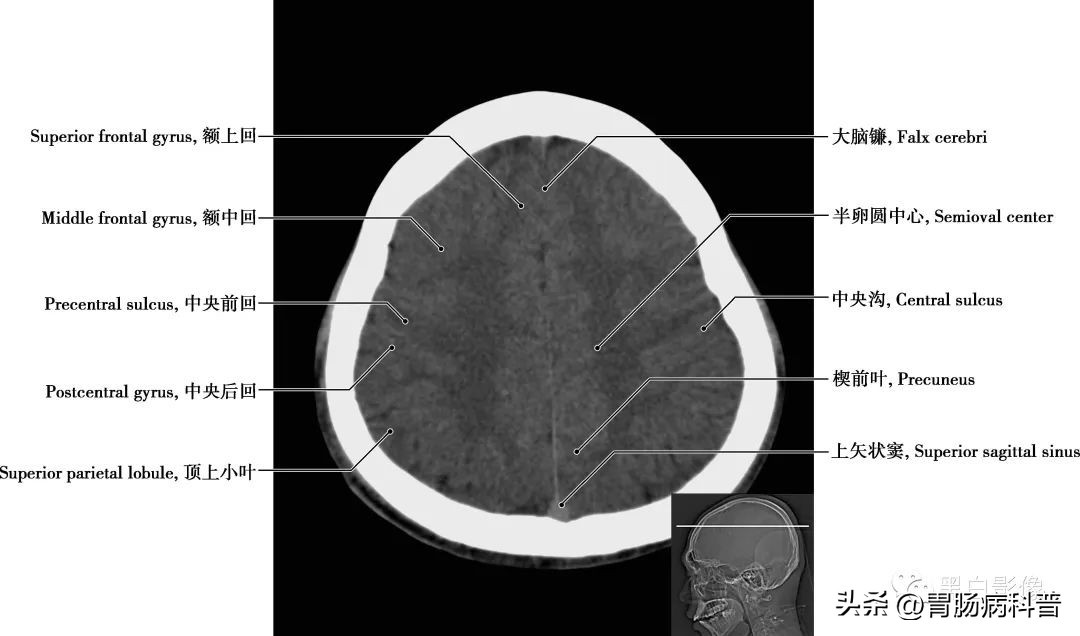

图1-1-5 经半卵圆中心轴位切面

额上回 在中央前沟的前方有额上沟和额下沟,被两沟分隔的是额上回、额中回和额下回。楔前叶 位于顶叶内侧部分,与许多高水平的认知功能有关,如情景记忆,自我相关的信息处理,以及意识的各个方面,但是并不确切